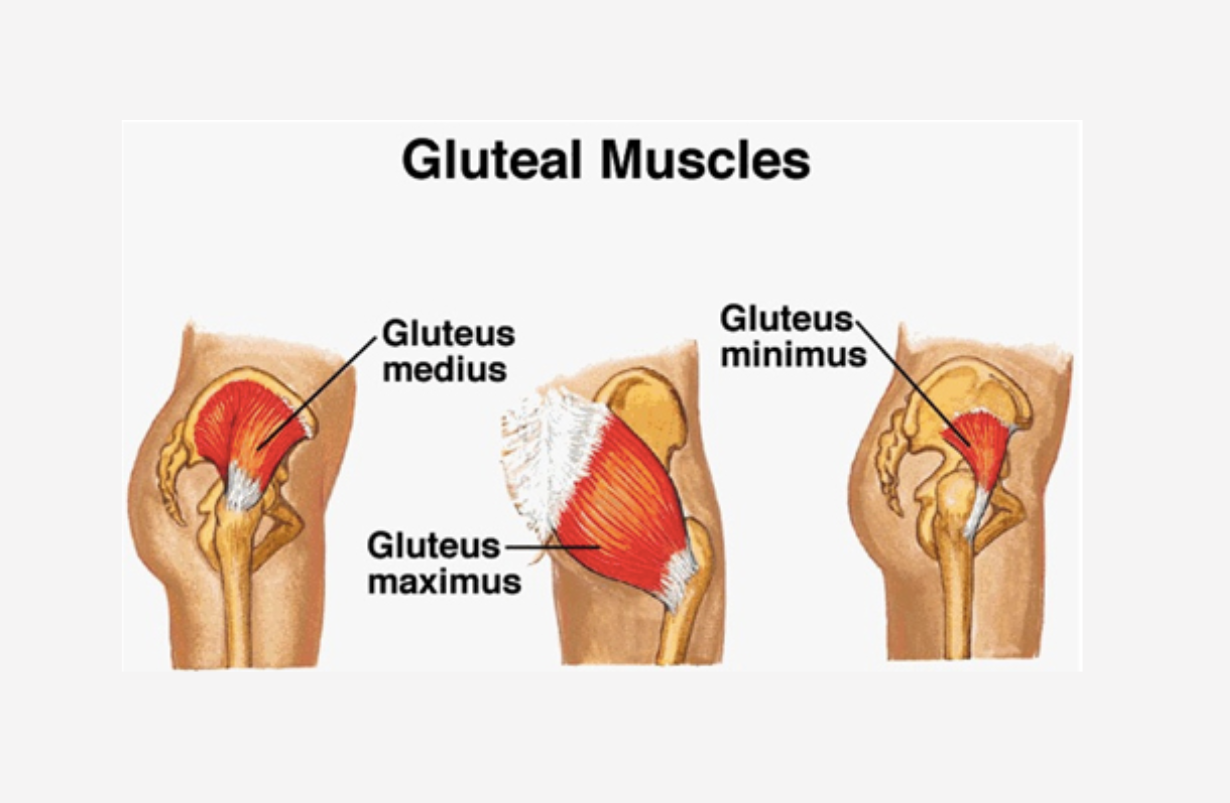

Torn Abductors

Hip abductors critical in walking, the gluteus medius and gluteus minimus are often torn, particularly in athletes in running sports and older and heavy women. Other abductors include the piriformis, the gemellus superior, oburator internis, gemellus inferior, quadratus femoris, and to a certain extent, the gluteus maximus. Serious tears of the gluteus medius and minimus come into play in all standing poses, but since few yoga poses adduct the thighs, few stretch these muscles directly. BENEFICIAL POSES: Salabhasana, Urdhva Dhanurasana, Mayurasana. EXPLANATION: Strengthening the gluteus maximus will take some strain off the medius and minimus, giving tears in the latter muscles a better environment in which to heal. REFERENCE: Kelley K, Slattery K, Apollo K. An electromyographic analysis of selected asana in experienced yogic practitioners. Mov Ther. 2018 Jan;22(1):152-158. doi: 10.1016/j.jbmt.2017.05.018. Epub 2017 May 31. Beazley D, Patel S, Davis B, Vinson S, Bolgla L.Trunk and hip muscle activation during yoga poses: Implications for physical therapy practice. Complement Ther Clin Pract. 2017 Nov;29:130-135. doi: 10.1016/j.ctcp.2017.09.009. Epub 2017 Sep 14.